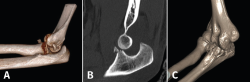

Figura 11. A: imagen en 3D de una fractura de tipo I de O’Driscoll con inestabilidad de codo, donde se observa además un fragmento de la cabeza del radio desplazado; B: imagen de tomografía axial computarizada (TAC) en un plano sagital. C: imagen de reconstrucción en 3D de una fractura de tipo II.